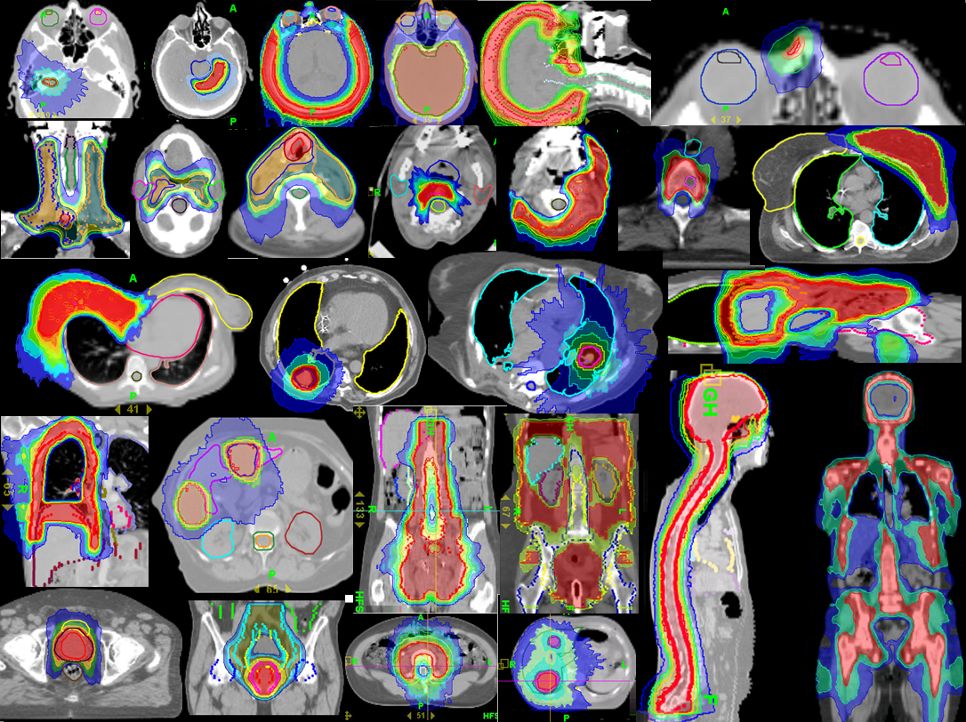

放射治疗是癌症治疗的常规方法,大约一半的患者在治疗过程中需要接受放射治疗,这种治疗使用高能辐射来缩小肿瘤并杀死癌细胞,然而传统意义的放疗不够精准,副作用较大,目前国内一些最新的放疗技术能够实现更精准的治疗。

托姆刀tomotherapy(螺旋断层放射治疗系统)是集IMRT(调强适形放疗)、IGRT(影像引导调强适形放疗)、DGRT(剂量引导调强适形放疗)于一体,并能准确地控制照射的强度、方向、针对癌细胞的形态、大小进行“精确射击”,是一种先进的肿瘤放疗设备,目前国内大型三甲医院已引进,日本开展的时间较早,有丰富的临床经验。

与其他放疗设备相比,托姆刀最大的优势就是治疗的适应症极广,病灶不规则,巨大,全身多发转移灶等普通放疗和质子无法处理的病灶都可以通过托姆刀治疗。详情点击:托姆刀突破了被医学界视为“天方夜谭”的放疗瓶颈!